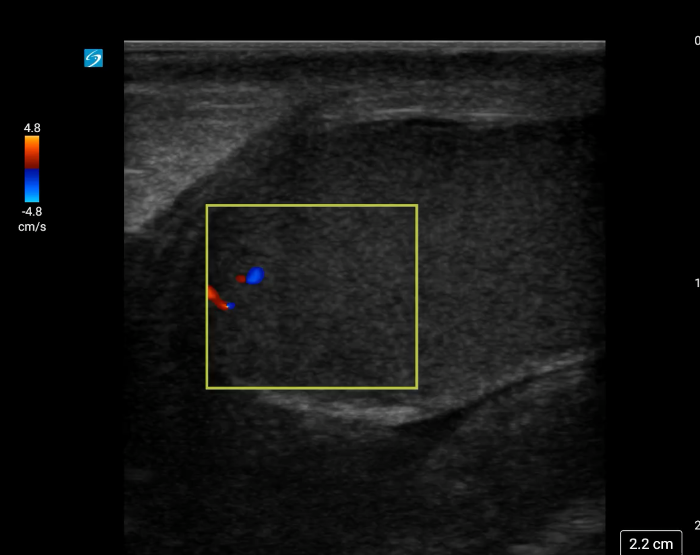

Image 1. Color Doppler of a testicle without blood flow to the body of the testicle concerning for testicular torsion.

In your first image (Image 1), you realize there is no flow with color Doppler. Additionally, you find a torsed cord complex (Image 2), also known as the “corkscrew sign.” You consult Urology who is busy in the operating room with another case. You decide to perform a manual detorsion due to your concern for testicular atrophy and risk of infertility. Using the open book technique, you get relief of pain and return of vertical positioning of the testicle after two rotations. On your repeat testicular POCUS with color Doppler you obtain these images (Images 3 and 4), which demonstrate venous and arterial flow throughout the testicle. The cord is now untwisted and appears linear in orientation.

- A testicle affected by torsion may appear larger due to swelling in the early stages. In the later stages, the testicle may appear atrophic with heterogenous echogenicity, due to ischemia, and may also contain a reactive hydrocele which appears as a hypoechoic fluid pocket around the testicle. (Video 4 and 5) Using color Doppler, you will see absent or significantly reduced blood flow to the body of the affected testicle. When unclear, compare to the unaffected side to appreciate a reduction in blood flow. You may try increasing the color with color Doppler to ensure there is no flow to the testicle.9

- Blood flow to the capsule of the testicle can be present during testicular torsion. It is important to focus on the intratesticular (body of the testicle) blood flow to avoid false reassurance.8